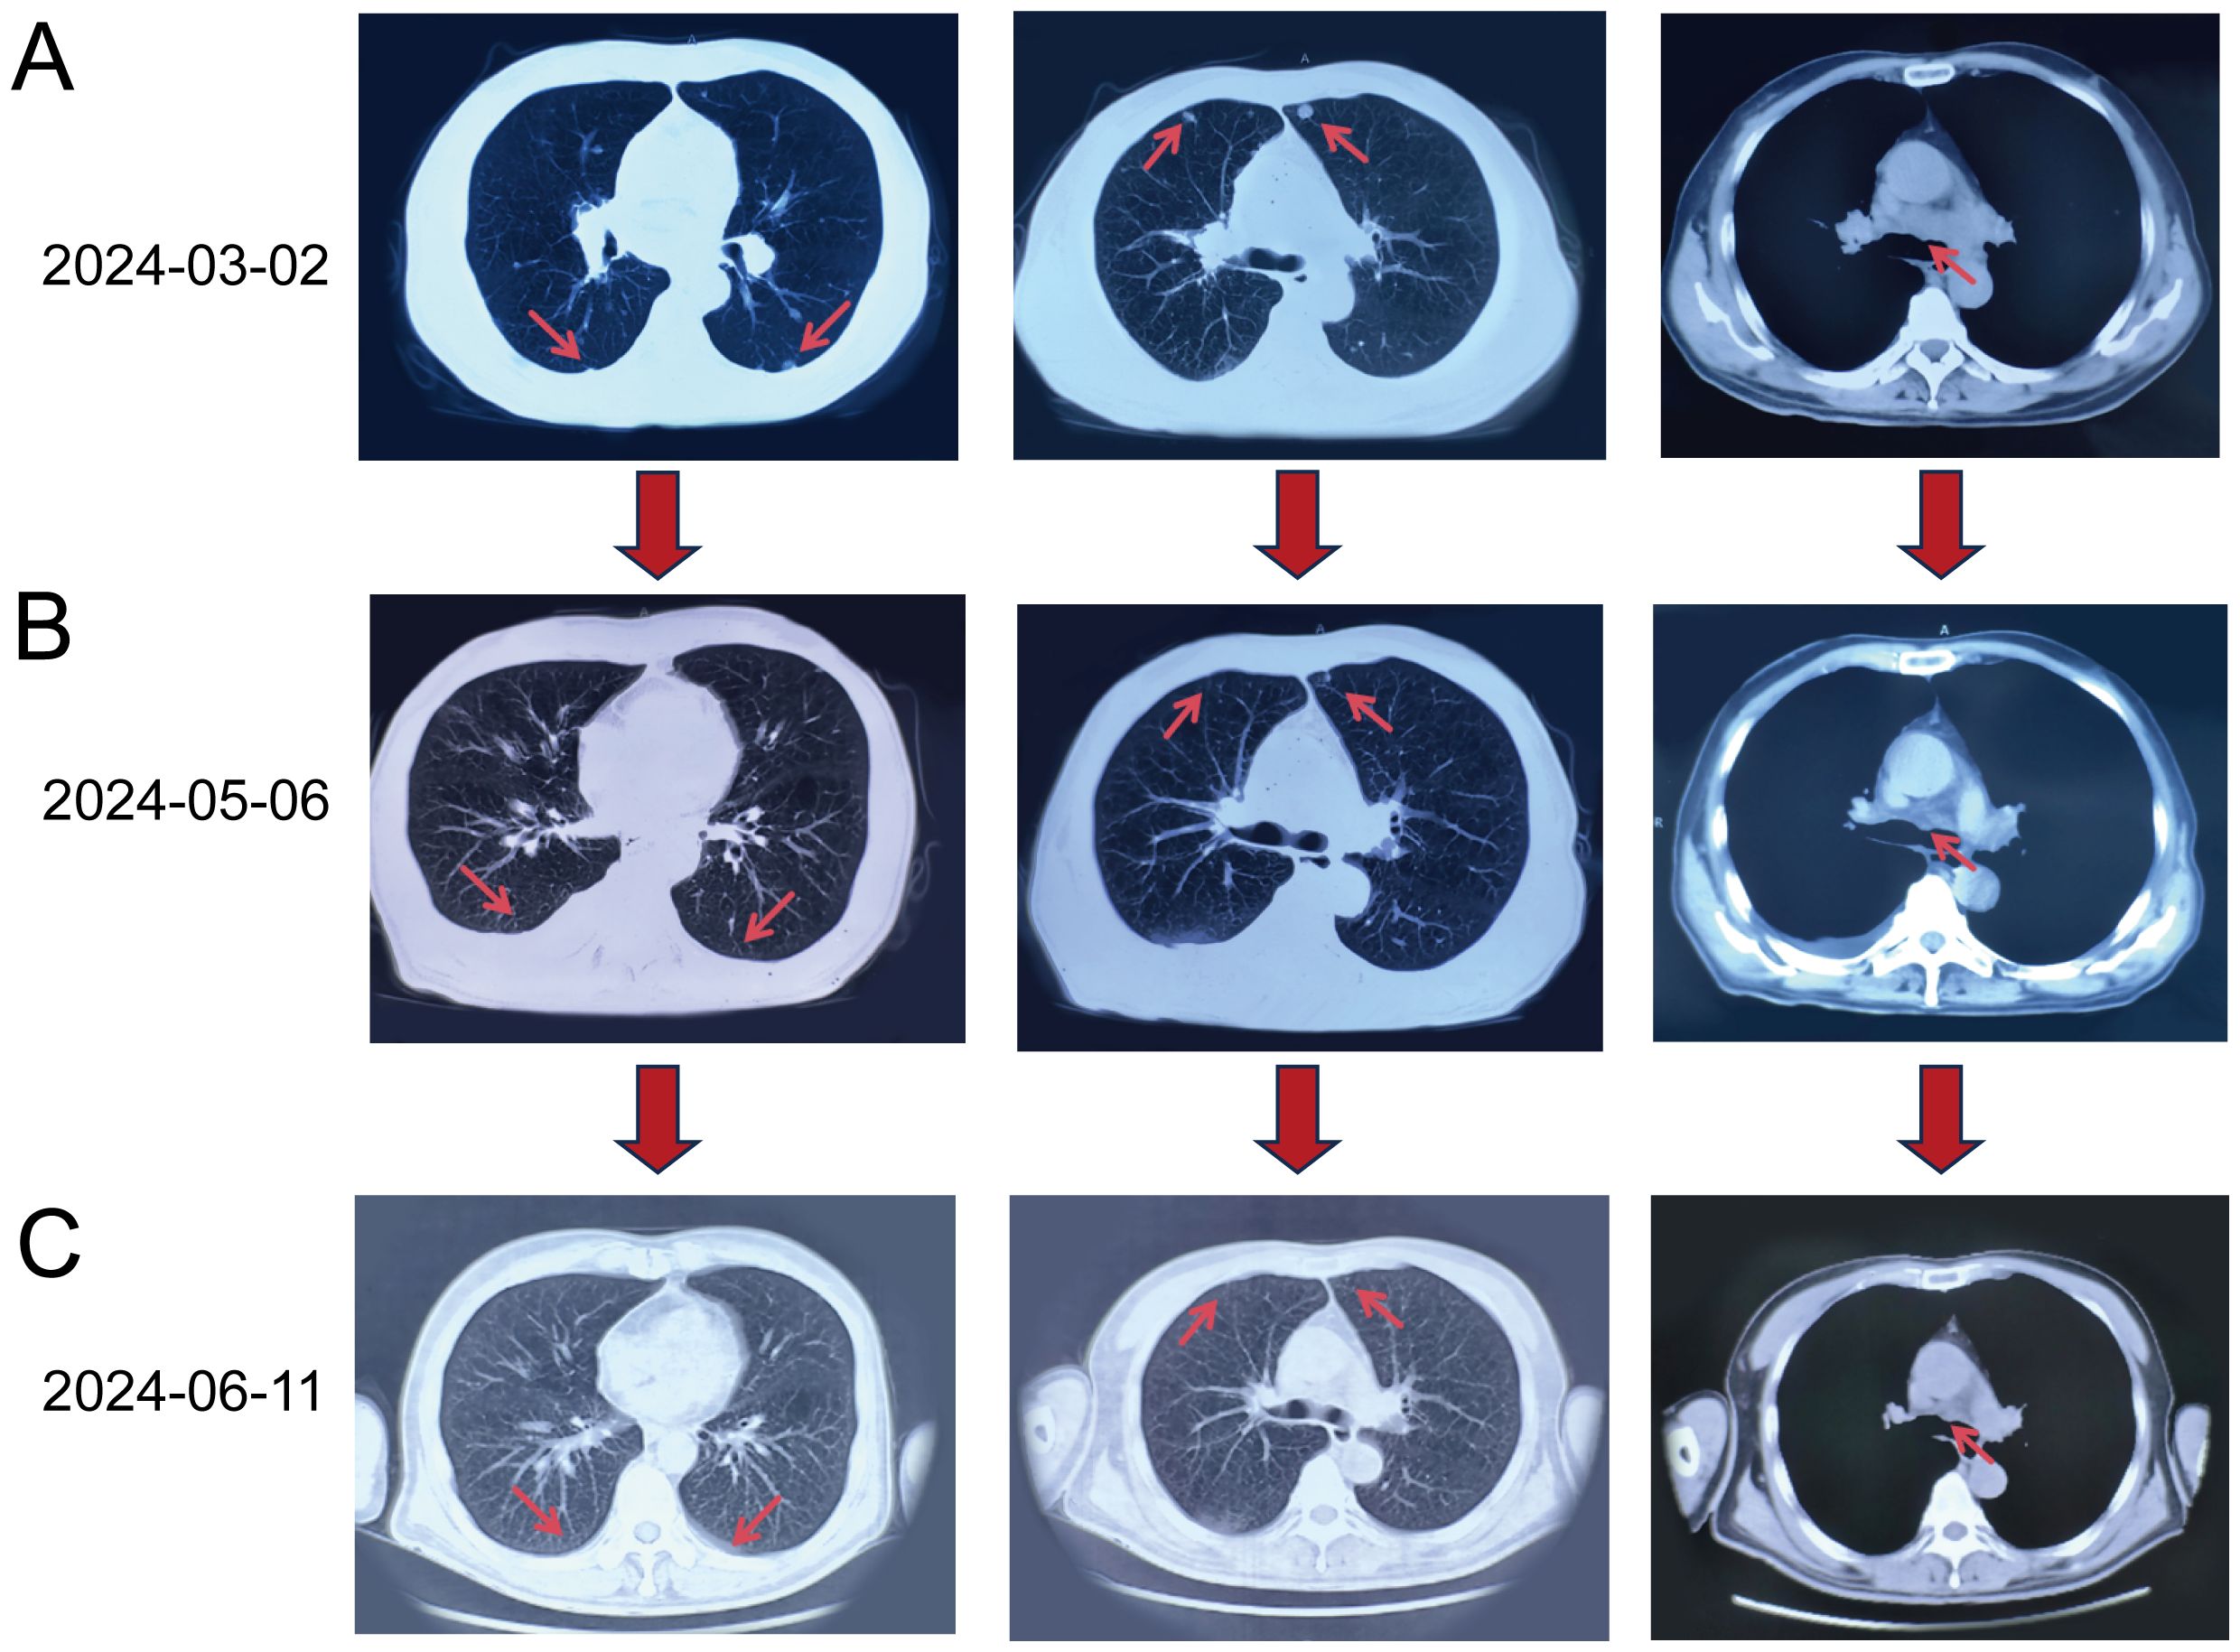

To confirm the complete response (CR), we conducted multiple imaging evaluations, including chest CT and PET-CT scans, which covered all known metastatic lesions. Follow-up imaging at different intervals (May 2024 and June 2024) demonstrated the complete resolution of the right upper lobe mass and absence of pulmonary nodules. Chest CT scans performed at multiple intervals (Figure 1) supported these findings. Furthermore, the levels of tumor markers, including CEA and CA-125, were also monitored and showed significant reductions, indicating a favorable treatment response. These comprehensive evaluations support the conclusion of a CR, consistent with the RECIST guidelines.

Figure 1. Chest CT scans obtained at different time points. (A) Baseline CT on March 2, 2024: Multiple nodular lesions (red arrows) in both lungs and enlarged mediastinal lymph nodes were visible. (B) Follow-up CT on May 6, 2024 (after four treatment cycles): Reduction in the size and number of pulmonary nodules (red arrows) and mediastinal lymph nodes (red arrow) was evident. (C) CT on June 11, 2024 (after six treatment cycles): Complete resolution of pulmonary nodules (red arrows) and further reduction in mediastinal lymph nodes (red arrow) were observed, indicating a complete response in the lungs.